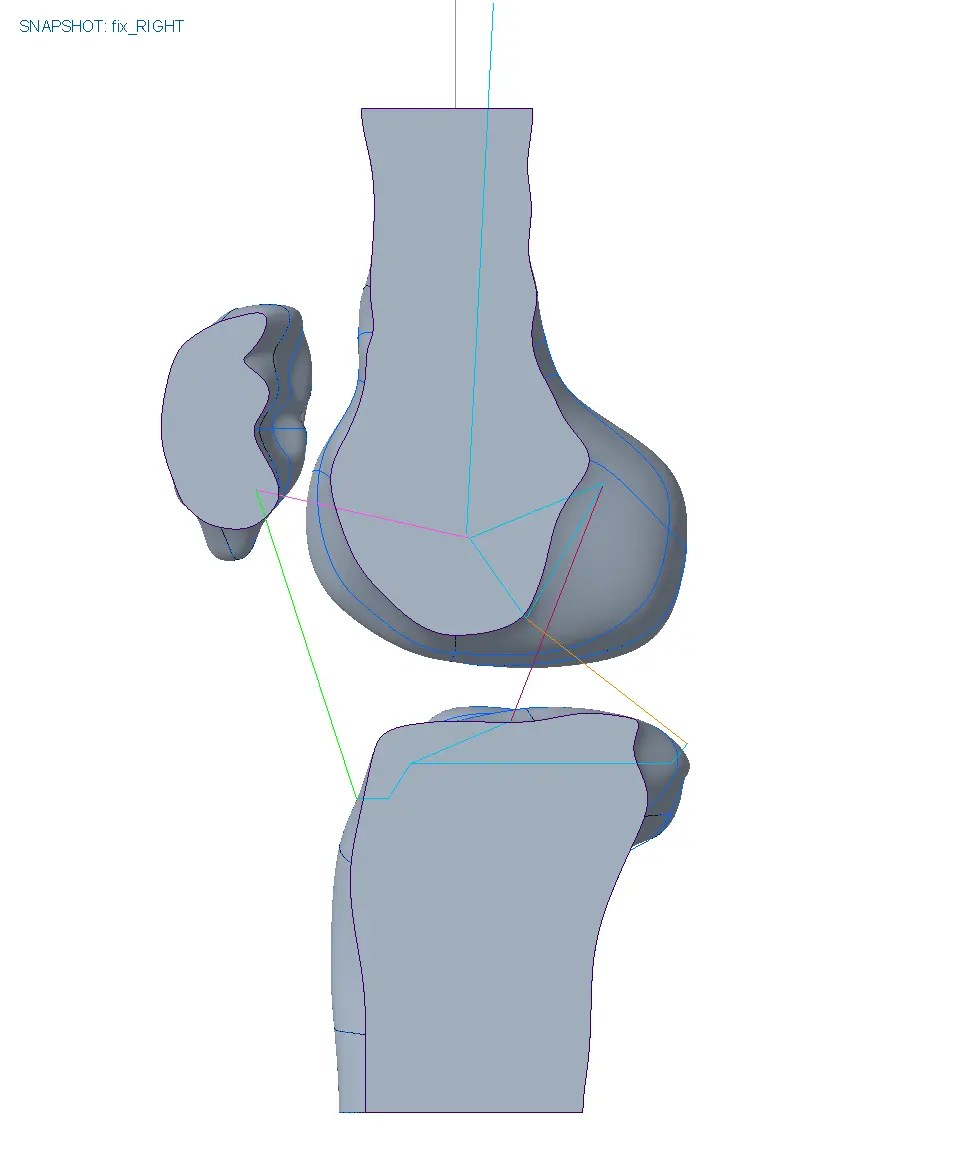

To give a more detailoed picture we built up a motion skeleton to move the bones and used the biomechanics of the knee to place the hinge and to create the design.

The motion designed brace fits like a gove and moves perfectly with the knee.

build frame

move knee

brace motion